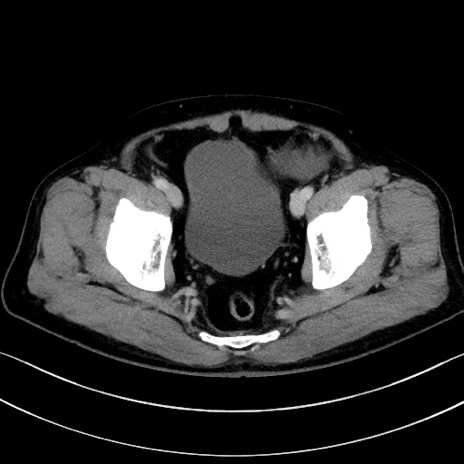

症例15(横断像)

【症例】70歳代男性

【主訴】腹痛

【現病歴】今朝から腹痛あり。全体的に痛い。特に左上の方。排ガスが今日はない。冷や汗が出る。

【既往歴】直腸癌術後

【身体所見】左側腹部〜上腹部に圧痛あり。腹膜刺激症状明らかなではない。軽度反跳痛。左下腹部に術後瘢痕あり。

【データ】WBC 7700、CRP 0.02